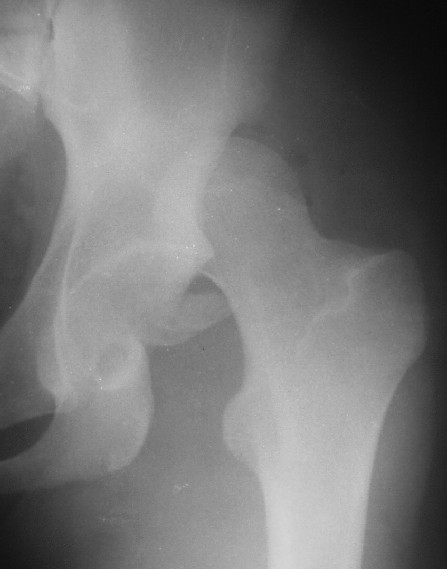

Уважаемые коллеги! Хотел-бы обсудить случай вывиха бедра с переломом вертлужной впадины.

Пациент 16-ти лет попал в ДТП 13.05.05г. Вывих вправлен в больнице по месту жительства в тот же день. Сегодня больной переведен в госпиталь. Вопросы:

Для определения тактики - обязательно - нужен снимок в боковой проекции, скорее операция, в послеоперационном периоде разгрузка, прогноз при правильном ведении - хороший.

Почему отличаются снимки в прямой проекции после вправления здесь и на дополнительном приложении ?

Прямая проекция от 19.05 по всей видимости выполнена с фиксацией деротационной повязкой, что отразилось на положении бедра, кроме этого существенно изменилась позиция таза в сагиттальной и горизонтальной плоскости (постельный режим, уменьшение болевого синдрома).

О диагнозе: в отсутствие КТ, КТ с 3D реконструкцией, с наибольшей вероятностью можно предположить, что откололся фрагмент заднего сектора вертлужной впадины. С позиции современных представлений о механике тазобедренного сустава указанный сектор не является опорным в вертикальном положении. Казалось бы, его необязательно репонировать и фиксировать, тем более размеры фрагмента малы: